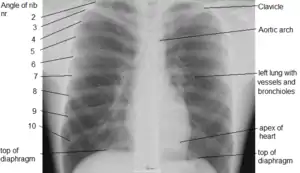

X-ray image of the chest showing the internal anatomy of the rib cage, lungs and heart as well as the inferior thoracic border–made up of the diaphragm.

The contents of the thorax include the heart and lungs (and the thymus gland); the major and minor pectoral muscles, trapezius muscles, and neck muscle; and internal structures such as the diaphragm, the esophagus, the trachea, and a part of the sternum known as the xiphoid process. Arteries and veins are also contained – (aorta, superior vena cava, inferior vena cava and the pulmonary artery); bones (the shoulder socket containing the upper part of the humerus, the scapula, sternum, thoracic portion of the spine, collarbone, and the rib cage and floating ribs).